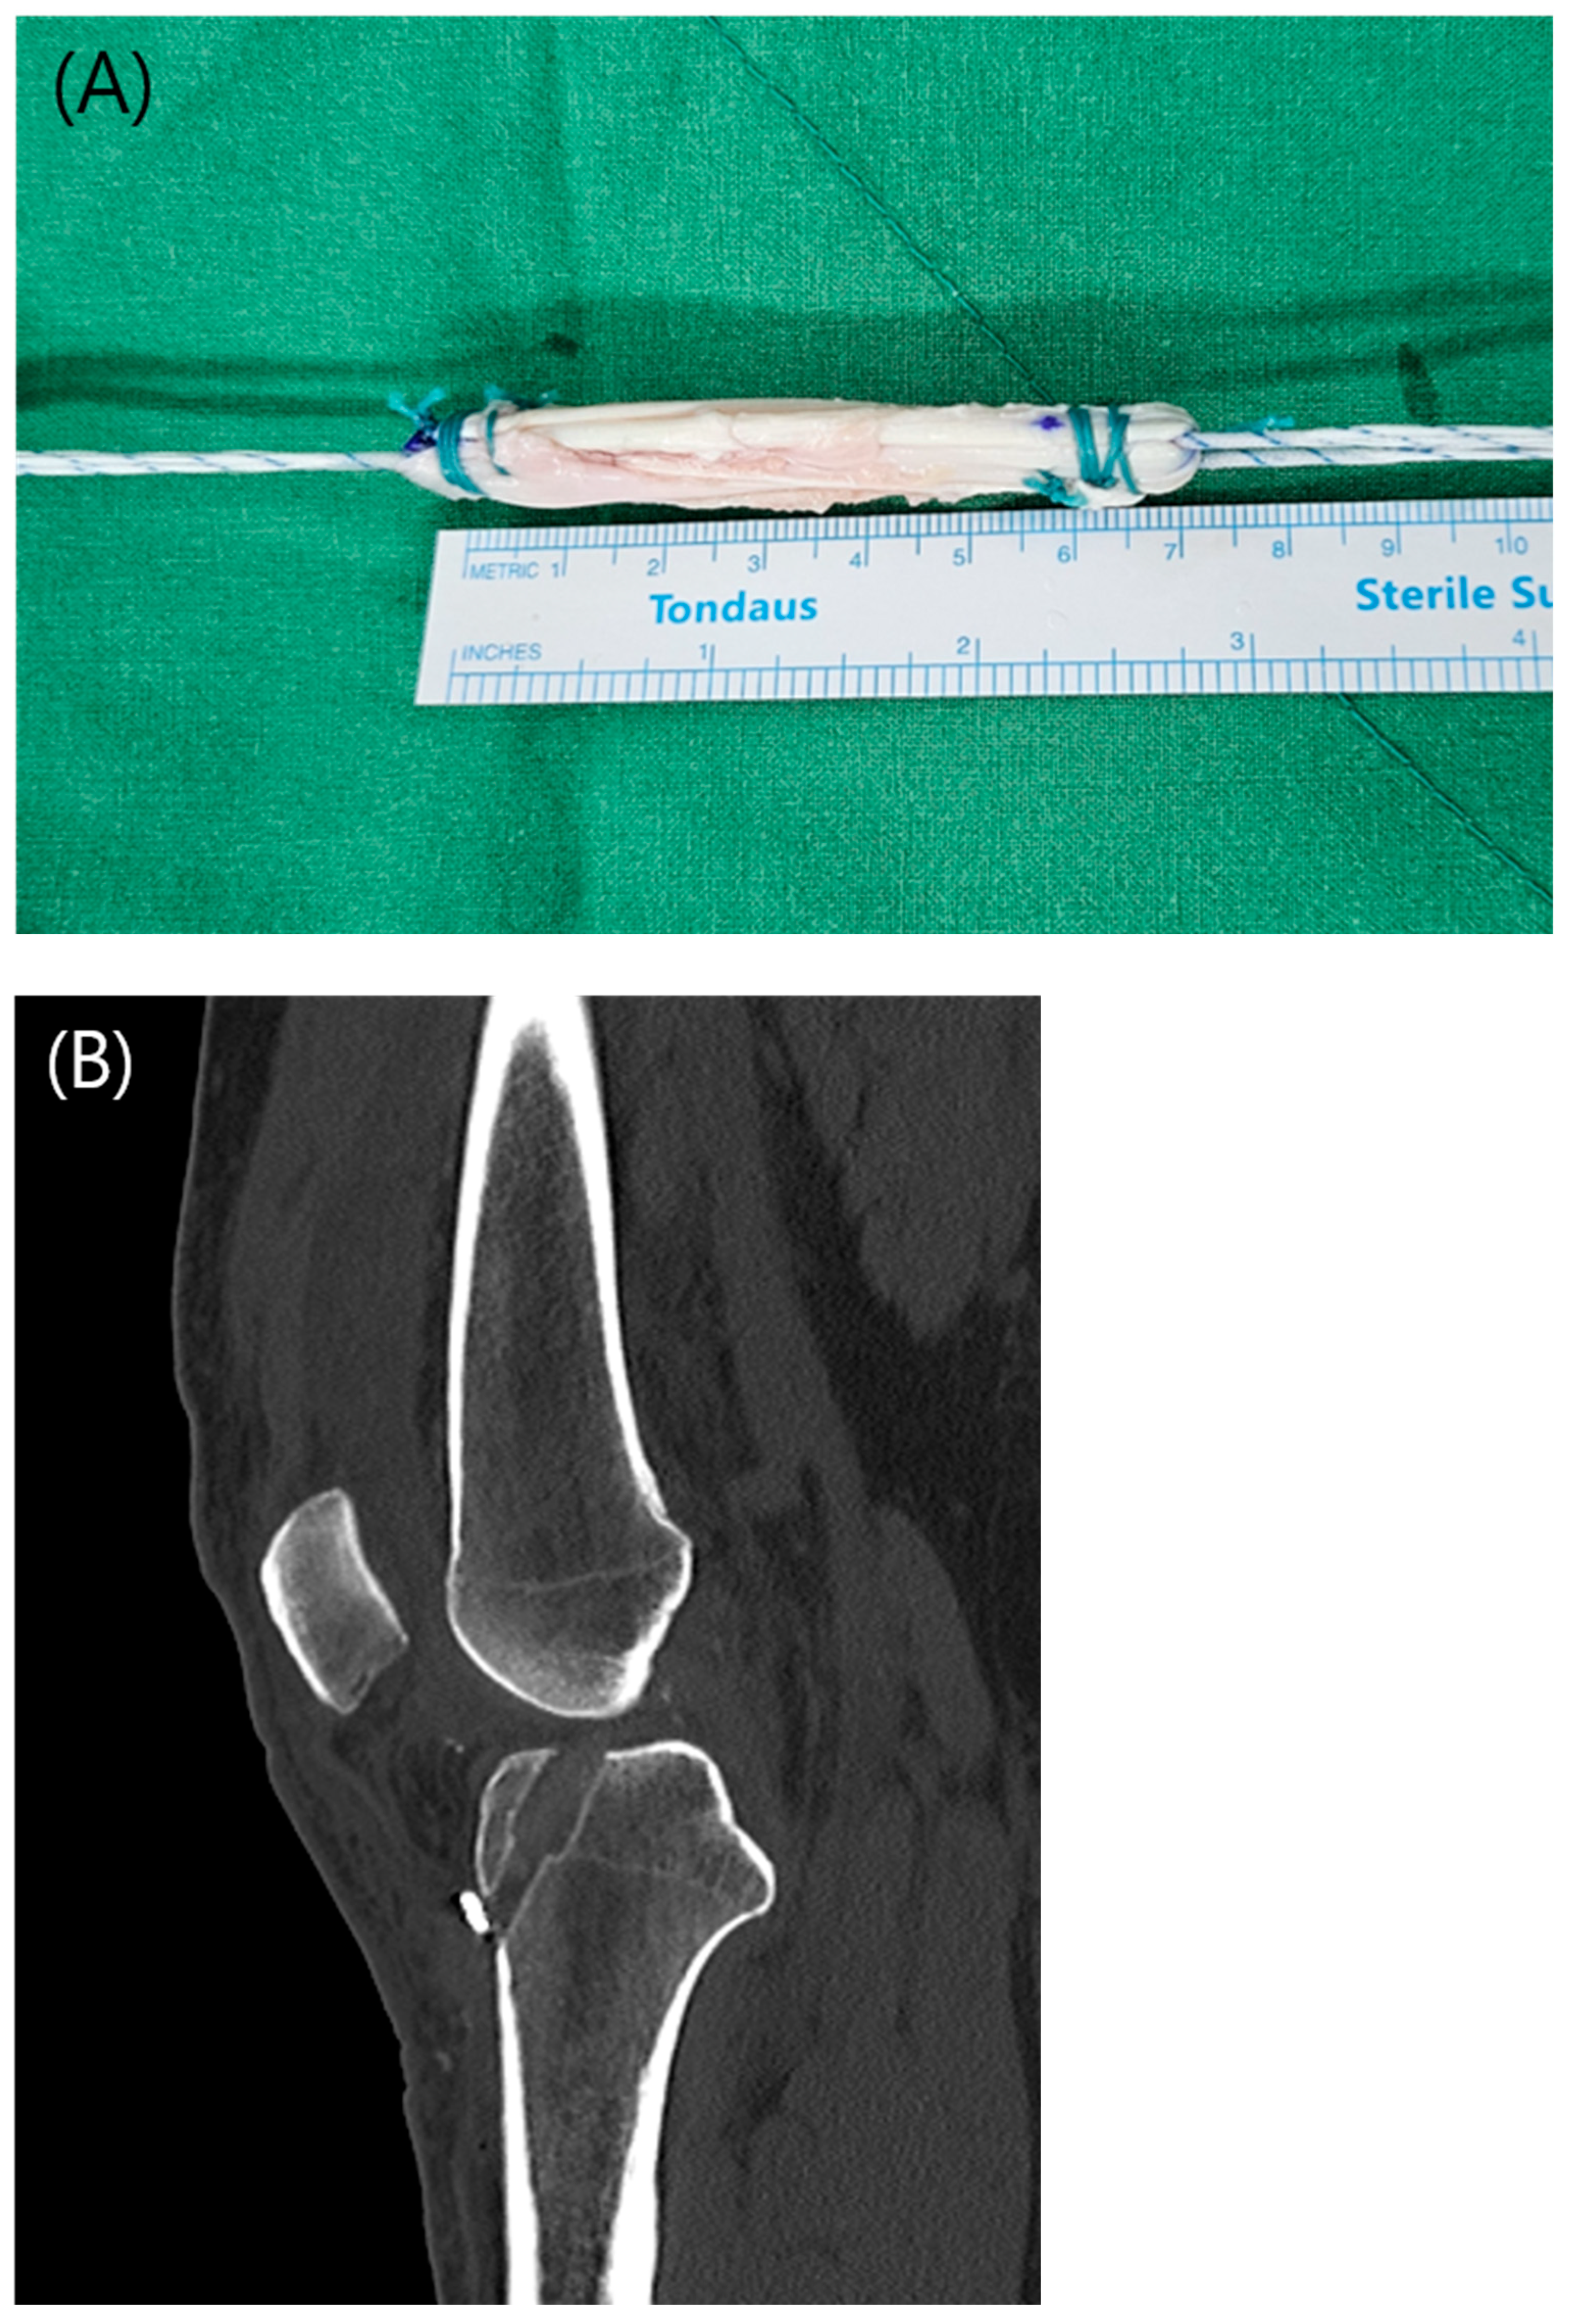

In the all-inside ACL reconstruction technique (AI-6 group), the graft was prepared using a triple-folded 6-strand hamstring autograft technique. Both the semitendinosus and gracilis tendons were harvested and whipstitched at both ends. Using a harvested hamstring length of approximately 22–25 cm, the final graft length was adjusted to approximately 7.5 cm (Figure 1(A)).

An adjustable cortical suspensory device was secured at each end of the folded graft to ensure proper fixation [17]. On the tibial side, the tibial socket was created in the AM bundle orientation at the native ACL footprint using a FlipCutter (Arthrex, Naples, FL, USA). To ensure that the combined length of the femoral tunnel, tibial tunnel, and intra-articular segment exceeded the total graft length, the angle of the tibial tunnel guide was adjusted accordingly (Figure 1(B)).

Figure 1. (A) Final construct of a 6-strand hamstring autograft. (B) Sagittal computed tomography image showing the configuration of the tibial tunnel after all-inside ACL reconstruction.